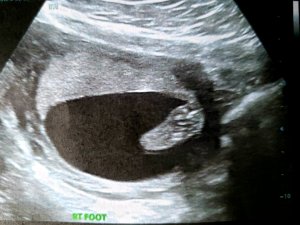

Since it’s now time for soup, Tylenol, and some more sleep, I’ll leave you with snapshots of my tenant’s spine, foot, and hands.